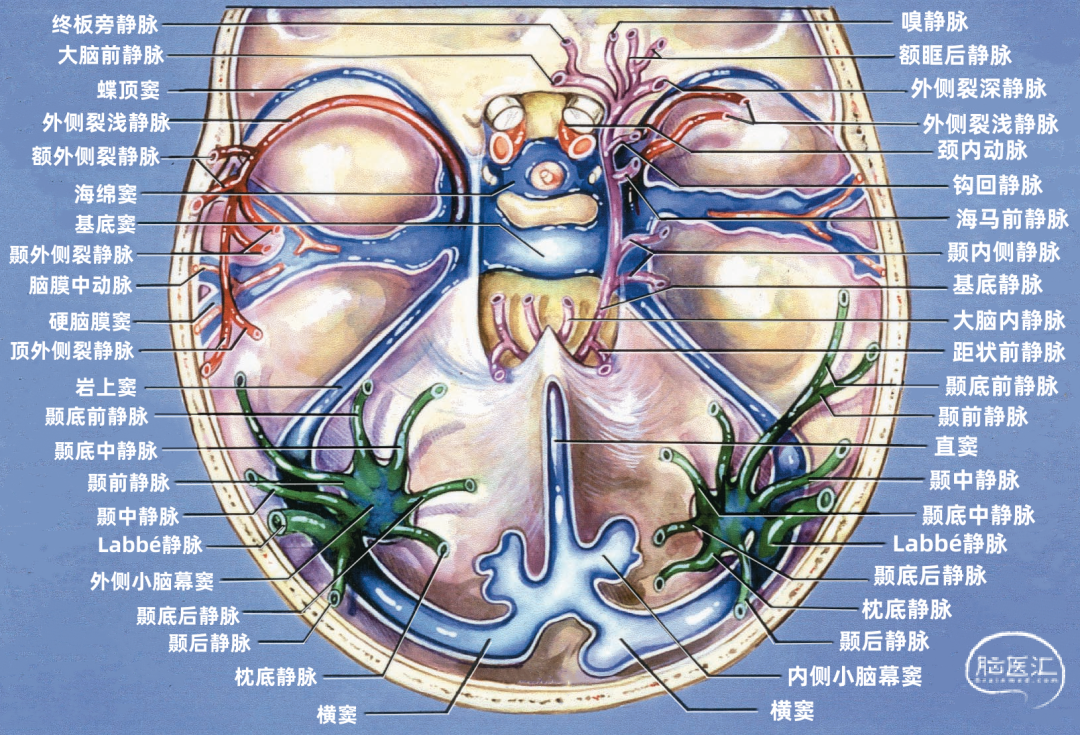

海绵窦(cavernous sinus)位于蝶鞍的两侧,并通过前、后海绵间窦跨越中线相连接。海绵窦状如海绵,内有许多小梁,血液可经海绵窦的间隙流过。每侧海绵窦前起眶上裂的内侧端,后抵颞骨岩部尖端,长约2cm,内外宽约1cm。上壁向内与鞍隔相移行;内侧壁上部与垂体囊相融合,下部以薄骨板与蝶窦为邻;外侧壁较厚,又分为内、 外两层,外层为致密结缔组织,内层为疏松结缔组织和网状纤维。海绵窦的冠状切面呈尖端略向下的三角形。 在前方,海绵窦与蝶顶窦和眼静脉相通;在中间,海绵窦通过经蝶骨大翼内侧面向外延伸的小静脉,穿过棘孔和卵圆孔,与翼状静脉丛相通;在后方,海绵窦直接开口于斜坡上的基底窦,并通过岩上窦连接横窦和乙状窦的交界处,通过岩下窦与乙状窦相连。▼11.岩上窦

蝶顶窦是与脑膜动脉伴行的最大硬脑膜窦,它在翼点水平以上与脑膜中动脉的前支伴行;在此水平以下,它离开动脉经蝶骨嵴下方的硬膜汇入海绵窦前部。它的上端通过硬脑膜静脉与上矢状窦相通。蝶顶窦有可能沿蝶骨嵴向下到达中颅窝底,而不进入海绵窦前部。 蝶顶窦可以向后汇入海绵窦,沿蝶骨大翼的外侧延伸;或者通过蝶骨导静脉,穿过中颅窝底与翼状静脉丛交通;这种蝶顶窦出颅骨连接蝶骨导静脉和翼静脉丛的变异被命名为“蝶基底窦”。 蝶顶窦还可以更向后走行进入岩上窦或横窦,这种沿中颅窝底向后走行汇入岩上窦或横窦的变异被命名为“蝶岩窦”。 侧裂浅静脉通常汇入蝶顶窦;但如果蝶顶窦发育不好或缺如,则侧裂浅静脉可直接进入海绵窦,或者向下围绕颞极和颞叶底面加入蝶基底窦或蝶岩窦。三、吻合静脉

▼3.外侧裂浅静脉

外侧裂浅静脉通常起自外侧裂后端,沿外侧裂唇行向前下。它可能以两支起始,但通常在沿蝶骨嵴进入静脉窦之前融合为一支。 外侧裂浅静脉接受额外侧裂静脉、顶外侧裂静脉和颞外侧裂静脉的回流,并经常与Trolard静脉和Labbé静脉相吻合。它穿经覆盖外侧裂前端的蛛网膜,在蝶骨嵴内侧部下方加入蝶顶窦,或直接进入海绵窦。它也有可能离开外侧裂,围绕颞极,进入中颅窝底的硬膜窦,引流入岩上窦,或通过蝶骨的小孔出颅与翼静脉丛相交通。 如果外侧裂浅静脉细小或缺如,则相邻的静脉将代替引流其区域。起自外侧裂上唇的静脉,向上引流加入进入上矢状窦的静脉;起自外侧裂下唇的静脉,直接向后下,汇入颞叶下方的硬膜窦。如果外侧裂浅静脉的中部缺如,则静脉前部加入蝶骨嵴的硬膜窦,而后部则加入Trolard和Labbé吻合静脉。

额叶底面(蓝色)由额极静脉、眶额前静脉、眶额后静脉,嗅静脉和终板旁静脉引流。 颞叶底面(绿色)由颞底前静脉、颞底中静脉、颞底后静脉、海马前静脉、钩回静脉、颞内侧静脉、颞外侧裂静脉。

额叶底面的静脉按引流方向由两种蓝色标出:浅蓝色为前组静脉,进入上矢状窦。深蓝色为后组静脉,进入基底静脉前端。额底静脉的前组是眶额前静脉;后组包括眶额后静脉和嗅静脉。 颞叶底面的静脉按引流方向由两种绿色标出:深绿色标注的静脉向外侧走行汇入小脑幕窦。浅绿色标注的静脉向内侧走行汇入基底静脉。向外侧走行的颞底静脉包括颞底前静脉、颞底中静脉、颞底后静脉;向内侧走行的颞底静脉包括海马前静脉、钩回静脉、颞内侧静脉。 枕叶底面只有一支即枕下静脉,由紫色标出,汇入小脑幕窦。大脑内静脉汇入Galen静脉。

下图示左侧前穿质下方区域的放大观。嗅静脉、大脑前静脉、额眶后静脉、外侧裂深静脉汇集形成基底静脉。脑室下静脉在大脑脚后缘汇入基底静脉。

颞叶静脉划分为:引流颞叶凸面的外侧组和引流颞叶底面的下组。 颞叶外侧组静脉还分为上升组,行向外侧裂。下降组,注入颞叶下方的静脉窦。上升组由颞外侧裂静脉组成,下降组由颞前、中、后静脉组成。 颞外侧静脉组及其引流区域如下:颞前静脉引流外侧面前1/3,颞上回除外;颞中静脉引流颞叶凸面中部;颞后静脉引流颞叶凸面后1/3,有时包括角回和顶叶前部;颞外侧裂静脉引流从颞极到外侧裂后端的颞上回。 颞下静脉分为:外侧组引流入小脑幕前外侧的窦;内侧组沿颞叶内侧缘,流入基底静脉。外侧组由前、中、后颞底静脉组成,颞底静脉好像放射状从枕前切迹发出,经过颞叶的下面。内侧组由钩回静脉、海马前静脉和颞叶内侧静脉组成。颞极附近基底面通常由颞外侧裂静脉引流。 颞下静脉及其引流区域如下:颞底前静脉引流颞底前1/3、颞枕回和邻近的海马旁回;颞底中静脉引流颞叶下面中1/3;颞底后静脉引流颞叶底面和枕叶前部;钩回静脉引流钩回和邻近的海马旁回:海马前静脉引流钩回后部和邻近的海马旁回;颞内侧静脉引流脑干上部旁基底池边缘的海马旁回。

五、引流静脉的分组

构成蝶骨嵴组(上图 红色)的桥静脉走行于蝶骨内表面的静脉窦。包括外侧裂浅静脉的终末支(包括额外侧裂静脉、顶外侧裂静脉和颞外侧裂静脉)和少数外侧裂深静脉,引流外侧裂附近的额叶、颞叶和顶叶的静脉血流。 这些静脉一般汇入蝶顶窦或海绵窦,少数进入蝶基底窦或蝶岩窦。 右侧的外侧裂浅静脉(下图 红色)直接进入蝶顶窦或海绵窦前部,而左侧的外侧裂浅静脉更靠后并进入海绵窦外侧部。侧裂深静脉和大脑前静脉也汇入基底静脉前端。颈内动脉行经海绵窦。中颅窝底的硬脑膜窦与脑膜中动脉伴行。

小脑幕组(上图 绿色)的桥静脉汇入行经小脑幕的静脉窦,即小脑幕窦或小脑幕附近的横窦和岩上窦。本组静脉引流颞叶外侧面和底面、枕叶的底面,包括颞底静脉、枕底静脉和来自颞叶外侧面的降静脉,如Labbé静脉。 除Labbé静脉外,这些静脉虽然有可能进入横窦,但大多数围绕半球的下缘汇聚于枕前切迹到达外侧小脑幕窦。而Labbé静脉通常汇入横窦。大脑底面的桥静脉汇入静脉窦之前,经常粘连于与中颅窝底硬膜和小脑幕表面。 从外侧面引流入小脑幕窦的静脉包括颞前静脉、颞中静脉、颞后静脉和Labbé静脉。

从下表面引流入小脑幕窦的静脉包括颞底前静脉,颞底中静脉、颞底后静脉和枕底静脉。 内侧小脑幕窦接受来自小脑的静脉血流,并加入直窦。基底窦位于斜坡。 大脑镰组(上图 紫色)由直接或经由大脑内静脉、基底静脉和大脑大静脉汇入下矢状窦或直窦的静脉构成。汇入直窦的静脉(上图 紫色)或其属支,引流胼胝体附近部分的额叶、顶叶和颞叶内侧部,此组静脉的引流区域大致相当于大脑边缘叶,包括终板旁静脉,额眶后静脉、嗅静脉、胼周前静脉、胼周后静脉,钩回静脉、海马前静脉、颞内侧静脉和距状前静脉。